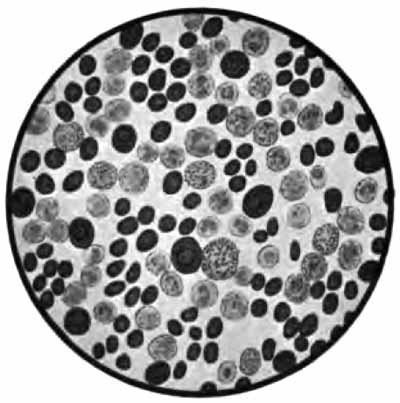

| PLATE II |

| FIG. 1.—Heart-failure cells in sputum, containing blood-pigment, from a case of cardiac congestion of the lungs (Jakob). |

|   |

| FIG. 2.—A, Sputum showing tubercle bacilli stained with carbol-fuchsin and Gabbet's methylene-blue solution (obj. one-twelfth oil-immersion); B, sputum of anthracosis, showing particles of coal-dust stained with methylene-blue (obj. one-twelfth oil-immersion) (Boston). |

In films stained by Gabbet's method tubercle bacilli, if present, will be seen as slender red rods upon a blue background of mucus and cells (Plate II, Fig. 2). They average 3 to 4 µ in length—about one-half the diameter of a red blood-corpuscle. Beginners must be warned against mistaking the edges of cells, or particles which have retained the red stain, for bacilli. The appearance of the bacilli is almost always typical, and if there seems room for doubt, the structure in question is probably not a tubercle bacillus. They may lie singly or in groups. They are very frequently bent and often have a beaded appearance. It is possible that the larger, beaded bacilli indicate a less active tuberculous process than do the smaller, uniformly stained ones. Sometimes they are present in great numbers—thousands in a field of the one-twelfth objective. Sometimes several cover-glasses must be examined to find a single bacillus. At times they are so few that none are found in stained smears, and special methods are required to detect them. The number may bear some relation to the severity of the disease, but this relation is by no means constant. The mucoid sputum from an incipient case sometimes contains great numbers, while sputum from large tuberculous cavities at times contains very few. Failure to find them is not conclusive, though their absence is much more significant when the sputum is purulent than when it is mucoid.

(2) Staphylococcus and Streptococcus (p. 262).—One or both of these organisms is commonly present in company with the tubercle bacillus in the sputum of advanced phthisis (Plate II, Fig. 2). They are often found in bronchitis, catarrhal pneumonia, and many other conditions.

(1) Pus-corpuscles are present in every sputum, and at times the sputum may consist of little else. They are the polymorphonuclear leukocytes of the blood, and appear as rounded cells with several nuclei or one very irregular nucleus (Fig. 8 and Plate II, Fig. 2). They are frequently filled with granules of coal-dust and are often much degenerated. Such coal-dust-laden leukocytes are especially abundant in anthracosis, where angular black particles, both intra- and extra-cellular, are often so numerous as to color the sputum (Plate II, Fig. 2, B). Occasionally mononuclear leukocytes are present.